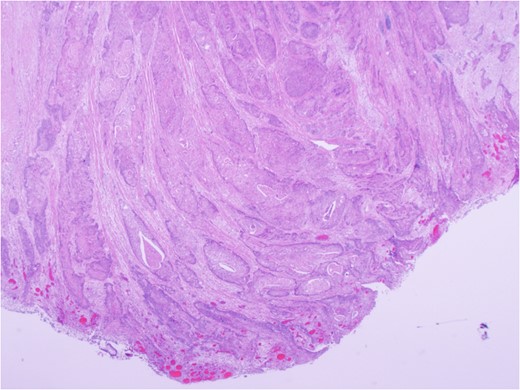

Urgent exploratory laparotomy revealed a large cecal mass invading the abdominal wall with perforation and localized abscess formation. A right hemi-colectomy was performed with irrigation and washout of the abdomen. Source control was achieved and a primary anastomosis was performed with no diversion. A Jackson-Pratt drain was left in situ. She received 3 days of IV antibiotics with transition to oral antibiotics on POD 4. Her JP drain was removed on POD 3 and she was discharged on POD 5 without complication and with a prescription for oral antibiotics. After extensive histopathology review, the cecal mass was confirmed to be an invasive squamous cell carcinoma of lung origin (Fig. 6). Specimens were sent for immunohistochemical staining. Subsequent investigations included cystoscopy and urine cytology, which were negative for urogenital carcinoma.

Carcinoma involving colonic serosa (image courtesy Dr Maisoun Abdelbaqi, Department of Pathology, Red Deer Regional Hospital, Alberta, Canada).

Accurate identification and characterization of GI metastasis is paramount to effective management. Imaging modalities such as CT or MRI are often inadequate for establishing the diagnosis [3]. As a result, accurate diagnosis relies heavily on immunohistochemical staining. A pathology review was performed in this case and should always be considered in this setting. For our patient, p16, TTF1, CK7, CK20, CDX2, PAX5 and NAPSIN A staining were completed on both lung and colonic tissue samples. Both samples were positive only for CK7, and the high degree of correlation allowed for confirmation of the diagnosis.